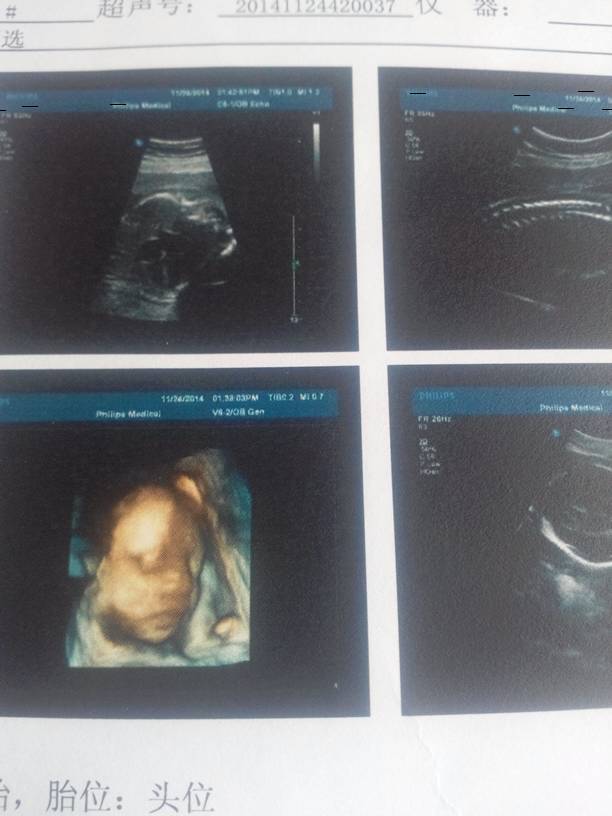

今天刚做的四维彩超,宝妈们帮我看看宝宝张的怎么样! 今天刚做的四维彩超,宝妈们帮我看看宝宝张的怎么样! 点击展开 亲亲宝贝喽 2014-11-24 17:22 为您推荐: 其他回答 你好,这个时候你应该关注的是那些数据,也就是说这些画面一下那些数据有没有出现什么异常?宝宝的相貌当然都是会具有一定的遗传性 夏未名末 2014-11-24 22:27 赞,漂亮的。 逸轩麻麻 2014-11-24 19:25 挺好看的,,,, 硪那麼小心ヽ還是丟了沵 2014-11-24 18:42 加油………… 琼瑶 2014-11-24 17:40 好宝宝。。 杨静 2014-11-24 17:39 加载更多 相关问题 今天四维彩超了,医生说是个儿子,我不想要,又没有可能医生四维彩超看错的宝妈?求助回复!!! 我刚突然想到了个名字,宝妈们帮我看看 好不好?有没有很多重名的啊?男宝 张宇轩 女宝 张雨萱 宝妈,医生,帮我看看,怀孕一个多月昨天去打B超医生说没事,一切很好,今天看裤子上面是这样的,不知道